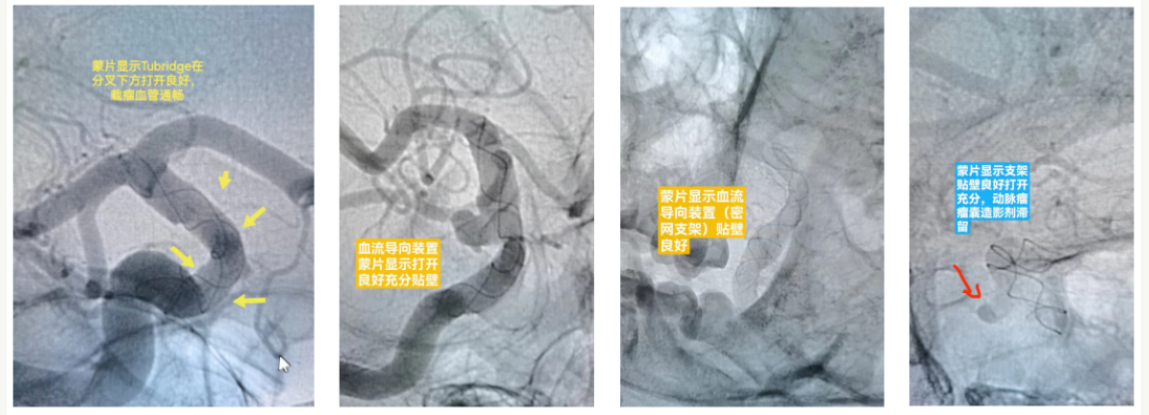

近日,黔南州人民医院神经外科成功为4名颅内未破裂动脉瘤患者实施了目前国内先进的血流导向装置置入术。

术前,黔南州人民医院神经外科团队充分评估、术前讨论、手术预案设计、围手术期规范管理、术前药物充分准备,排除了相关手术禁忌后确定为患者实施血流导向装置置入术。在征得患者及家属同意后,先后为4名患者成功实施血流导向装置植入术,目前患者均已病愈出院。

血流导向装置是通过改变载瘤动脉内的血流方向以减少或降低动脉瘤内的血流冲击,达到动脉瘤瘤体内血液滞留和血栓形成的目的,最终在血流导向装置的表面和动脉瘤瘤颈处形成新生内皮细胞,实现动脉瘤的完全闭塞和治愈。

血流导向装置的治疗范围从以往的颈内动脉大型和巨大型动脉瘤,发展至小型、破裂、后循环、远端小血管动脉瘤,是众多复杂颅内动脉瘤治疗的首选方法。